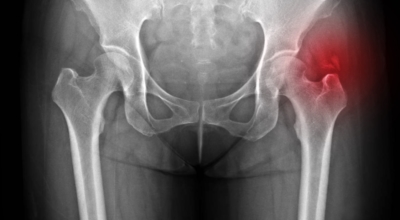

3. 고관절 통증 증상 원인 - 퇴행성 관절염

나이가 들면 예사로 발생되는 질환 중 한 종류입니다. 관절을 지켜주고 있는 연골의 손상이나 퇴행성 변화로 인해 관절을 이루는 뼈와 인대 등에 손상이 생겨 염증과 통증이 나타나는 질환입니다. 고관절 쪽 연골이 닳게 되면서 망가지게 되고 또 쉽게 없어지지 않는 통증에 시달릴 수 있답니다.